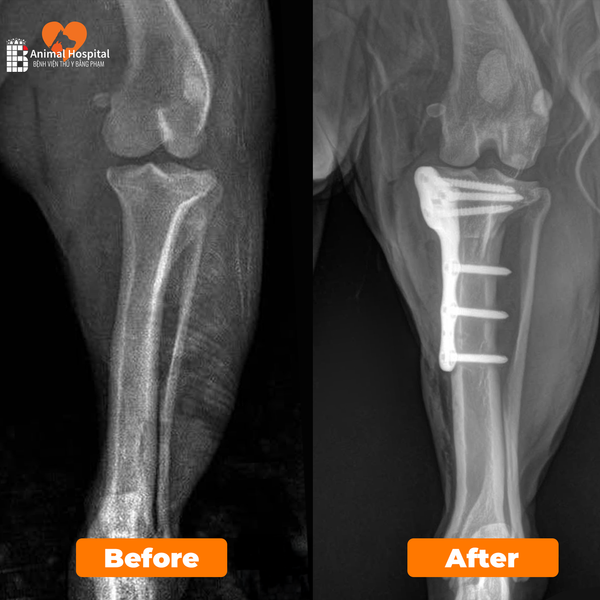

Đội ngũ bác sĩ Bệnh viện Thú y Bằng Phạm hội chẩn và thống nhất thực hiện phẫu thuật TPLO (Tibial Plateau Leveling Osteotomy) kết hợp chỉnh trật xương bánh chè.

• Nẹp cố định: 6.5R TPLO Plate

Trong quá trình phẫu thuật, ghi nhận rãnh ròng rọc kém phát triểnsụn khớp không bao phủ hoàn toàn, và dây chằng chéo trước đã bị đứt hoàn toàn.

Phẫu thuật TPLO được tiến hành thành công, giúp tái định hướng lực tác động lên khớp gốiổn định lại mâm chày.

Ca phẫu thuật TPLO kết hợp chỉnh trật xương bánh chè được đánh giá thành công, khớp gối ổn định, phục hồi chức năng tốt, không ghi nhận biến chứng hậu phẫu.